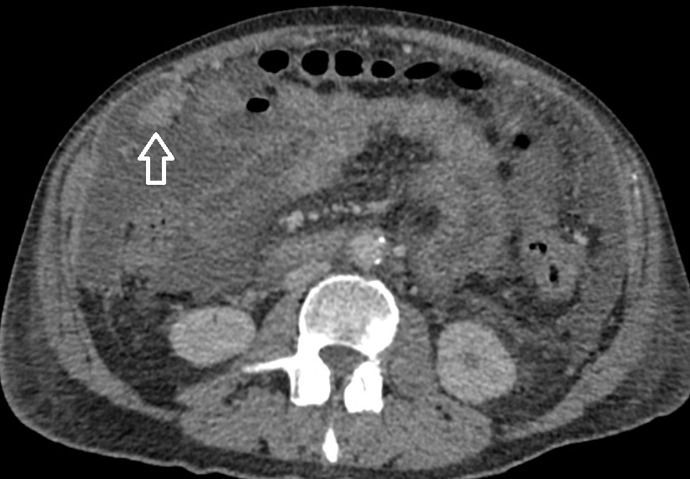

Feminino,67 anos, apresentando dor abdominal difusa, associada à perda ponderal e ascite.

Carcinomatose Peritoneal

Os implantes peritoneais são massas de tecidos moles que aparecem como nódulos solitários ou múltiplos. Os nódulos podem coalescer para formar placas que revestem as vísceras. Essas placas aparecem como áreas de espessamento irregular dos tecidos moles. Grandes placas omentais são chamadas de bolos omentais (omental cake). Os implantes podem realçar com o contraste intravenoso e podem calcificar. Alguns implantes são de baixa atenuação e mimetizam fluido loculado. Os locais comuns de metástases incluem hemidiafragma direito, fígado, calha paracólica direita, intestino, omento e pelve.

No abdome, os implantes na superfície diafragmática aparecem como espessamento nodular ou semelhante a placa do diafragma. O envolvimento do fígado e do baço resulta em recorte da superfície por massas com menor atenuação do que o parênquima em exames com contraste. Os ligamentos falciforme, gastro-hepático e gastroesplênico podem parecer espessados e mostrar encalhe de tecidos moles. Os tumores podem ser vistos na porta hepática, fossa da vesícula biliar e saco menor e na superfície do estômago. Espessamento irregular e nodularidade ocorrem nas goteiras paracólicas. Há infiltração da gordura omental por tumor de atenuação de tecidos moles. Nódulos discretos também podem estar presentes e podem ser distinguidos do intestino porque não estão conectados às alças adjacentes. Massas de tecidos moles no intestino e no mesentério podem aderir as alças e causar obstrução intestinal. A obstrução intestinal é o tipo mais comum de morbidade secundária ao câncer de ovário, ocorrendo em 51% dos casos. As lesões mesentéricas aparecem como espessamento da raiz com um padrão estrelado e irradiado. A extensão da doença omental para a parede abdominal anterior resulta em massas periumbilicais.